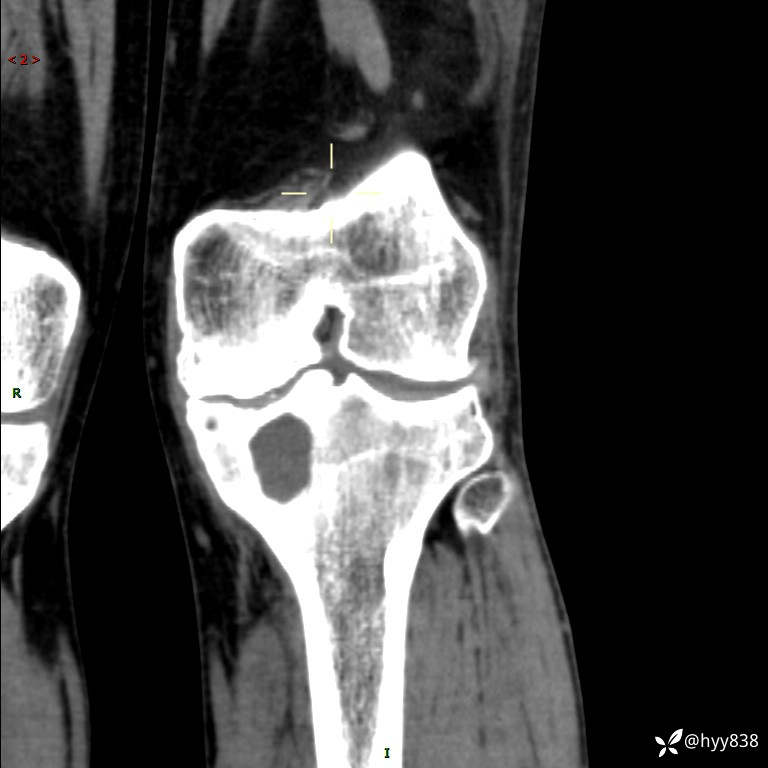

CT

干骺端溶骨性病变病灶周广泛水肿